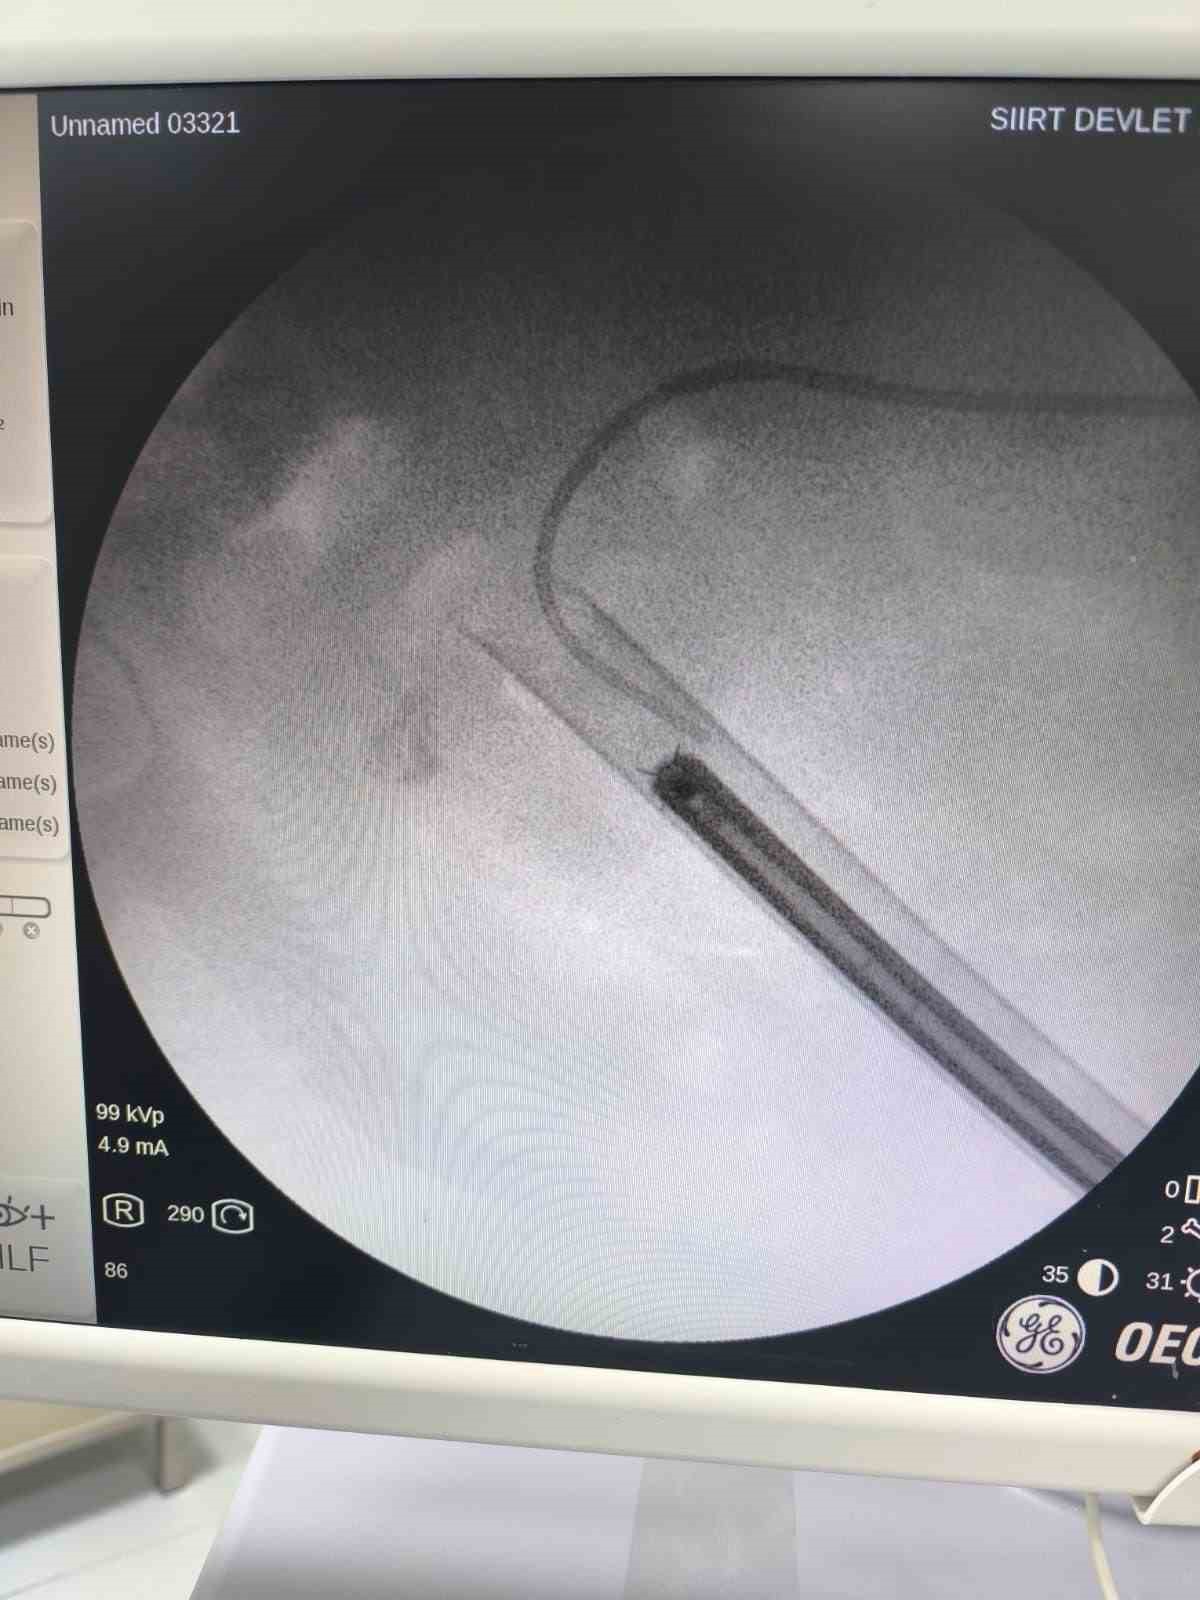

Siirt’te 34 yaşındaki Fatih Aslan, ateş, üşüme ve idrar yaparken yanma şikayetleriyle hastaneye başvurdu. Yapılan muayene ve testlerin ardından piyelonefrit (böbrek iltihabı) tanısı konuldu ve enfeksiyon tedavisi tamamlandı. Üroloji uzmanı doktor Miraç Ataman, gerçekleştirilen operasyon, hem tıbbi açıdan hem de toplumsal sağlık açısından önemli bir başarı olduğunu söyledi. Ataman, "34 yaşındaki erkek hastamız, ateş, üşüme ve idrar yaparken yanma şikayetleri ile acil servise başvurdu. Yapılan değerlendirme sonucunda piyelonefrit (böbrek iltihabı) tanısı konuldu ve yatış yapılarak enfeksiyon tedavisi başarıyla tamamlandı. Tanı sürecinde yapılan Bilgisayarlı Tomografi (BT) görüntülemesinde böbreğin tamamını kaplayan, sert yapıda(950-1450 HU), literatürde staghorn olarak adlandırılan ve halk arasında ‘ geyik boynuzu taşı ’ diye bilinen büyük taş saptandı. Staghorn taşlar böbreğin tüm boşluklarını doldurup, tekrarlayan enfeksiyonlara ve uzun vadede böbrek fonksiyon kaybına yol açabildiğinden tedavisi hayati önem taşımaktadır. Biz de bu vakamızda, Perkütan Nefrolitotomi (PCNL) yöntemiyle böbreğe küçük bir cilt kesisi üzerinden girerek endoskopik cihazlarla taşları parçalayıp çıkardık. PCNL, özellikle çapı 2 cm’den büyük ve kompleks taşlarda altın standart kabul edilmektedir. Normalde staghorn taşların temizlenmesi uzun süren ve çoğu zaman birden fazla seans gerektiren zorlu bir süreçtir. Modern altyapısı sayesinde, ciltten tek giriş yolu açılarak yaklaşık 1,5 saatlik bir seansta böbreğin tüm taş yükü başarıyla temizlendi" dedi.